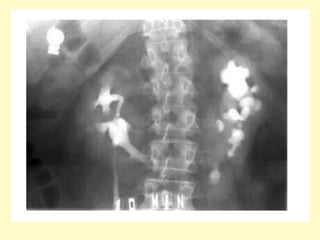

4-Prune Belly Syndrome :

-Rare anomaly comprising a specific constellation of

features

-It consists of three major findings :

1-Gross ureteric dilatation

2-Anterior abdominal wall underdevelopment (resulting in

the prune belly appearance)

3-Bilateral undescended testes (cryptorchidism) in males

-There is often an association with other respiratory,

gastrointestinal, musculoskeletal, and cardiovascular

anomalies

-It is also known as Eagle Barrett syndrome or triad

syndrome

-Urinary tract abnormalities include :

1-Bilateral hydroureteronephrosis: often with

extremely dilated, tortuous ureters

2-Varying degrees of renal dysplasia

3-Enlarged urinary bladder, often with urachal

diverticulum

4-Vesicoureteral reflux is common

5-Poor bladder contractility

6-Dilated posterior urethra without urethral

obstruction